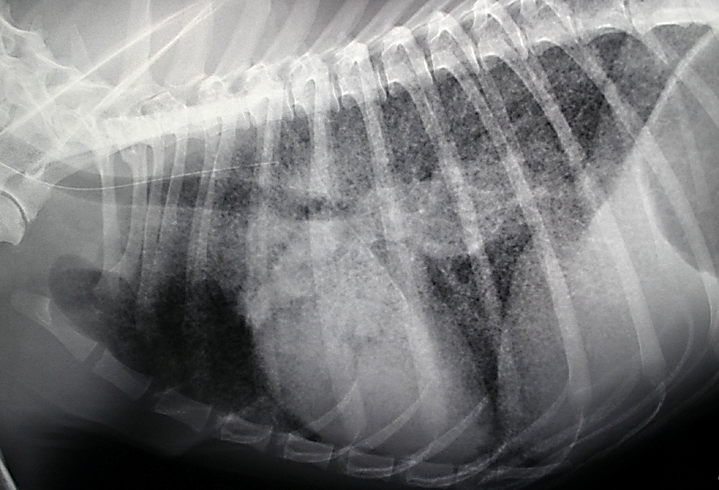

Рентгенодиагностика бронхопневмонии: Советы и примеры

Раздел: Альбом открытий